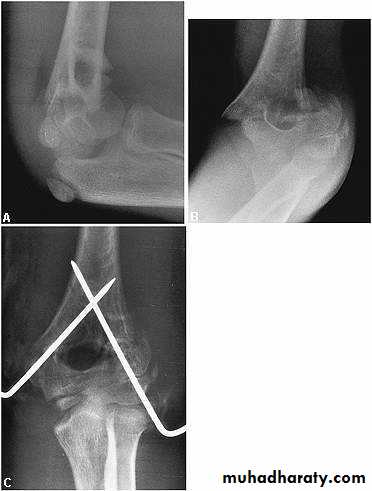

Grade three (completely displaced fract.) :

Manipulation under anesthesia if fail then do close pining or open reduction and fixation by k-wires .

Indications of open reduction :

1- closed fracture can not reduced by manipulation .

2-open fracture .

3- associated vascular damage .

The manipulation , the cubitus varus deformity